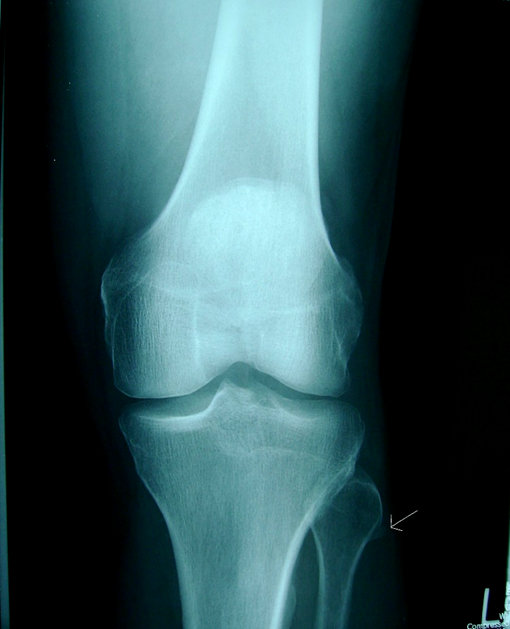

Table Abbreviations: Nerve conduction studies (NCS) A radiograph taken at the time of clinical presentation of the left knee revealed an osteophytic spur on the lateral proximal fibula in the transition area from the fibular head to the neck (Figure 1)

Figure 1: Patient’s left knee radiograph depicting a 1cm lateral fibular osteophyte (arrow).

The most common reported etiology of osteophyte associated fibular neuropathy is multiple exostosis syndrome (MES) [1]. This autosomal dominant disease begins in childhood and is cited to cause peripheral nerve entrapments [11, 12]. Nerve compression of any peripheral nerve is rare in childhood MES, described as occurring in less than 1% of all cases [13]. The fibular bone exostoses occur in 8.2% of childhood MES and associated nerve compression is rare [14]. The frequency of exostosis involvement of the fibular head in adults has not been previously described and its association with fibular neuropathy is reported in this case. This case describes an osteophyte protruding from the fibular head area (Figure 1) as a probable contributing cause of fibular neural injury. The presentation is complicated because of remote fibular nerve trauma 34 years earlier. The patient reported complete motor recovery and normal AT function without foot drop for over 32 years.